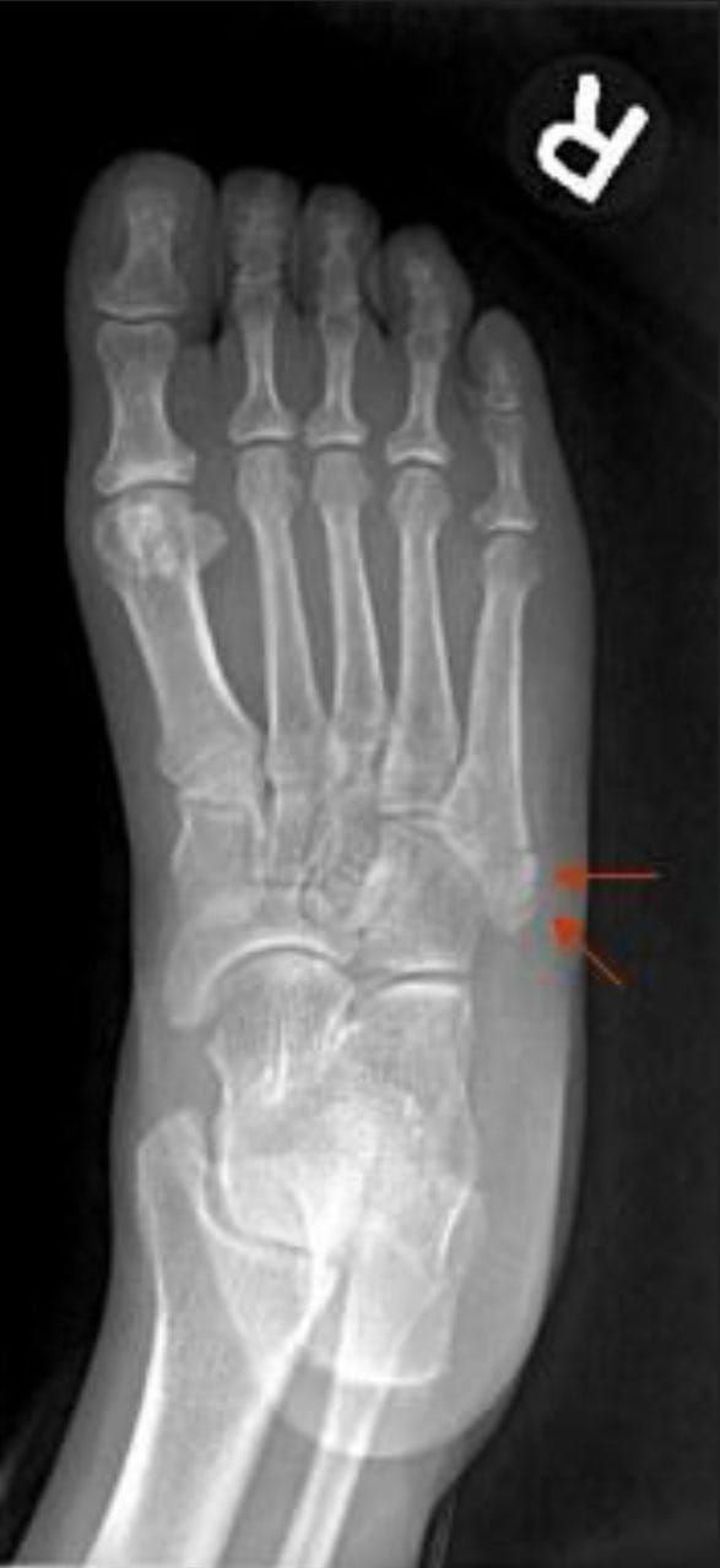

Zone 1 (pseudo Jones fx) ▪️Proximal tubercle (rarely enters 5th tarsometatarsal joint) ▪️Due to long plantar ligament, lateral band of the plantar fascia, or contraction of the peroneus brevis ▪️Nonunions uncommon

# 5th metatarsal